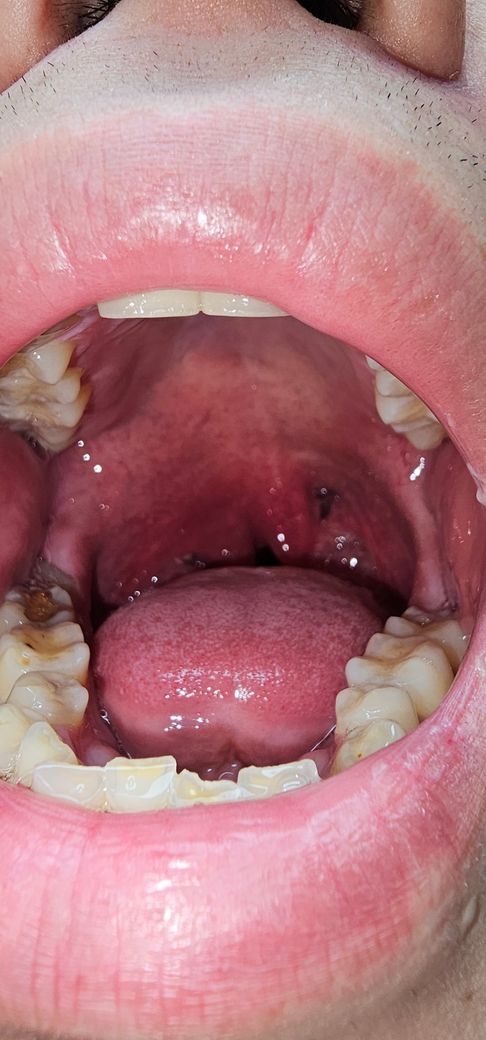

편도염증 및 붓기로 인한 호흡곤란..

한시가 급합니다 .. 일요일이라 문연병원도 없어서 자세한 건 사진으로 대체 하겠습니다 . 증상과 해결방법좀 알려주세요 ...ㅠ

• 1번 째 사진

올려주신 사진이 저명하진 않지만 편도가 커져 있는 것이 확인 됩니다.

편도 비대로 인한 호흡곤란이 있다면 응급실 진료를 받으시기 바랍니다.

• 급성편도염의 가능성이 있어보입니다

세균성이 아니라면 염증을 제거하고 증상 완화를 위한 적절한 보존적 치료를 시행하면됩니다. 필요하면 진통제를 투여하는데, 대부분의 경우 아세트아미노펜(acetaminophen) 제제나 아스피린 계열의 약물만으로도 충분합니다. .세균성 편도염을 치료하기 위해서는 전신적인 항생제 치료가 필요하기에 전문의 진료를 받는 것이 필요합니다.

항생제를 투여하기 시작했다면 7~10일간 충분히 쓰는 것이 좋습니다

• 호흡곤란이 있다면 진료를 받으셔야 합니다

지금은 응급실 진료만이 가능하실 것 같습니다

환자분 혼자서 시간을 지연시키지 마시고 일단 응급실로 가보시기 바랍니다.